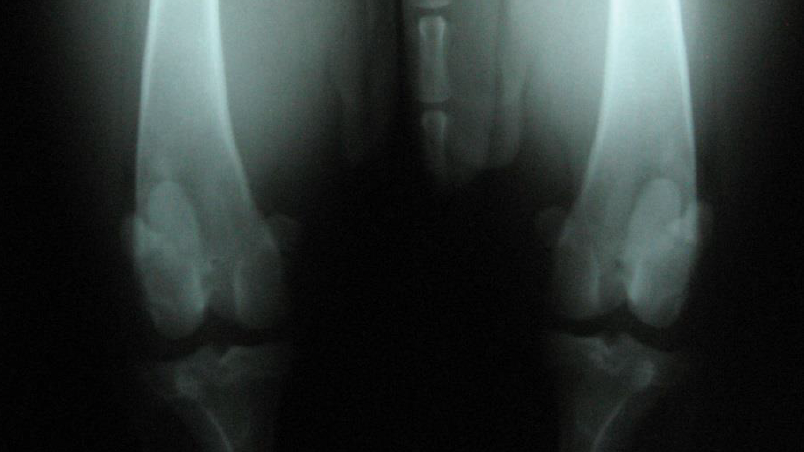

Im Gegensatz zum Menschen liegt beim Hund meist kein akutes Trauma, sondern ein degenerativer Prozess mit Vorschädigung des Bandes vor. Diagnostisch reichen die Möglichkeiten von der klinischen Untersuchung über Röntgenaufnahmen bis zu CT, MRT oder Arthroskopie. Unbehandelt steigt das Risiko für Arthrose und Meniskusschäden deutlich.